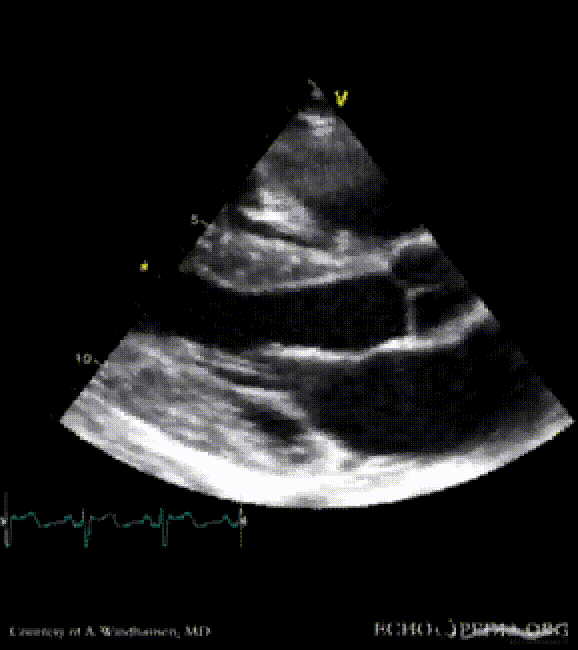

Severe Hypertrophic Cardiomyopathy (HCM)

Case description: Severe Hypertrophic Cardiomyopathy (HCM)

Courtesy of: A. Windhausen, AMC, The Netherlands